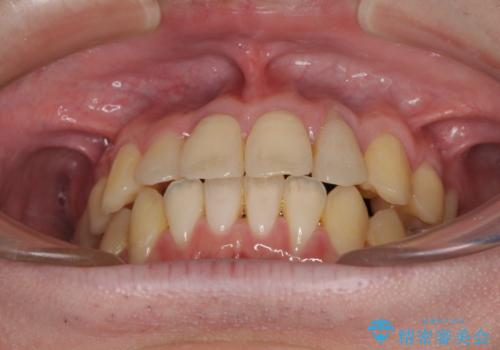

前歯のクロスバイト インビザラインによる矯正治療

- 上下のクロスバイトと前歯のデコボコを気にして来院された患者様です。

インビザラインを用い、IPR(歯と歯の間を削る)と歯列全体を拡大させることで、歯並びを整えていくこととしました。

上下ともに歯列全体を後方に移動させるため、上下の親知らずを抜歯することとしました。

奥に位置していた上の前歯が下の前歯を乗り越える際、奥歯でものを咬むことができず、辛い時期が続きました。